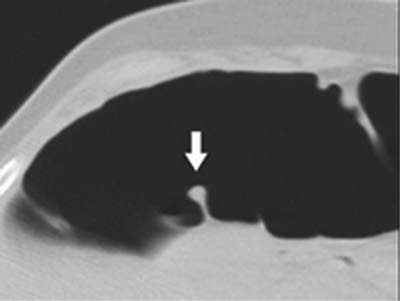

| Left to right: prone and supine axial images of a flat tubular adenoma along the fold of the hepatic flexure. The lesion was missed by both radiologists, but detected by CAD (represented by lines in image at left). From Fletcher JG, Summers RM, Johnson CD, MacCarty RL, Wilson LA. Lessons in Detection: Contribution of Computer-aided Detection with Perceptively Challenging Lesions at CT Colonography. Supplement to Radiology November 2002, Vol. 225, p. 304. RSNA December 1-6, 2002, Chicago. Image courtesy of Dr. Joel Fletcher, © Mayo Medical Foundation, 2002. |